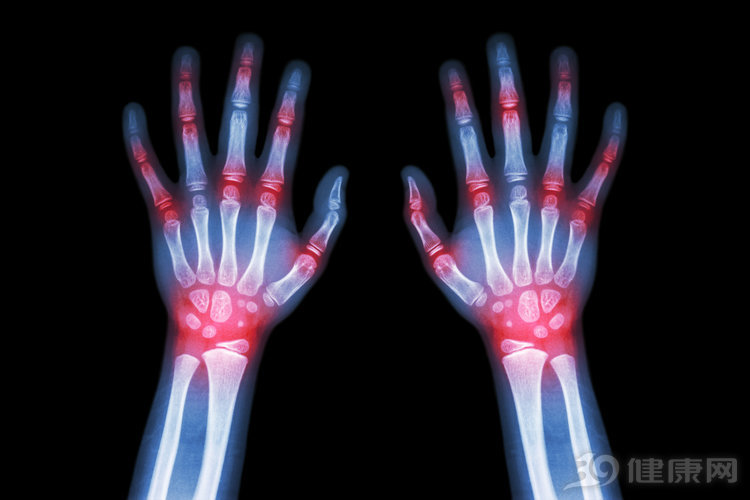

除了上文所说的带有刀割撕裂等强烈感之外,膝关节痛风还会使人全身无力,甚至出现头疼,发热等现象。在这个时期,关节滑膜水肿充血,膝关节肿痛总是反复发作,逐渐形成慢性关节炎。慢性关节炎会使膝关节出现畸形僵硬的病状,同时导致关节韧带侵蚀,骨质可能会被破坏。